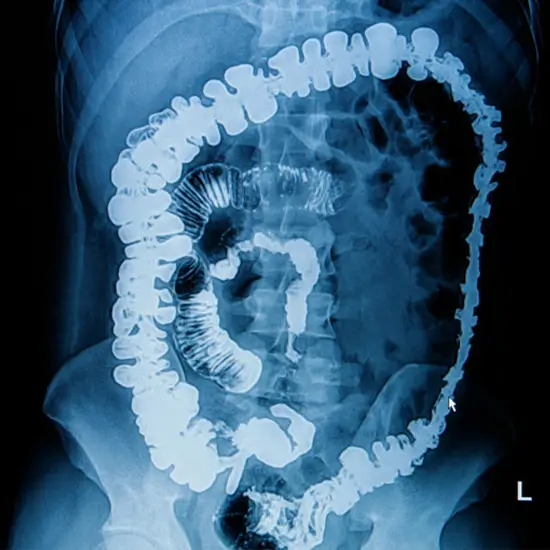

Barium Meal Follow Through

What is an X-ray Barium Meal Follow Through Test?

The barium meal follow-through test is an imaging test to diagnose small bowel disorders. This test helps diagnose Crohn's disease, ulcerative colitis, and colon cancer.